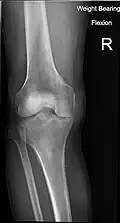

Radiography to examine possible fractures after a knee injury

Knee fractures are rare but do occur, especially as a result of a road accident. Knee fractures include a patella fracture, and a type of avulsion fracture called a Segond fracture. There is usually immediate pain and swelling, and a difficulty or inability to stand on the leg. The muscles go into spasm and even the slightest movements are painful. X-rays can easily confirm the injury and surgery will depend on the degree of displacement and type of fracture.